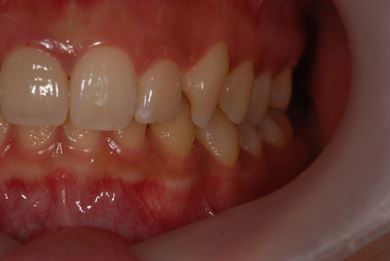

| 性別/年齢 | 女性 / 21歳 | ||||||||||||||||||||||||||||||||

| 主訴 | 歯の変色、欠けた部分を治したい。 | ||||||||||||||||||||||||||||||||

| 治療方針 | 上前歯を根管治療後、オールセラミッククラウンにて審美的回復を行う。 | ||||||||||||||||||||||||||||||||

| 治療内容 | オールセラミッククラウン2本(オールセラミック用土台2本) | ||||||||||||||||||||||||||||||||

| 総治療費 | 286,650円 | ||||||||||||||||||||||||||||||||

| 治療期間 | 4ヶ月 |